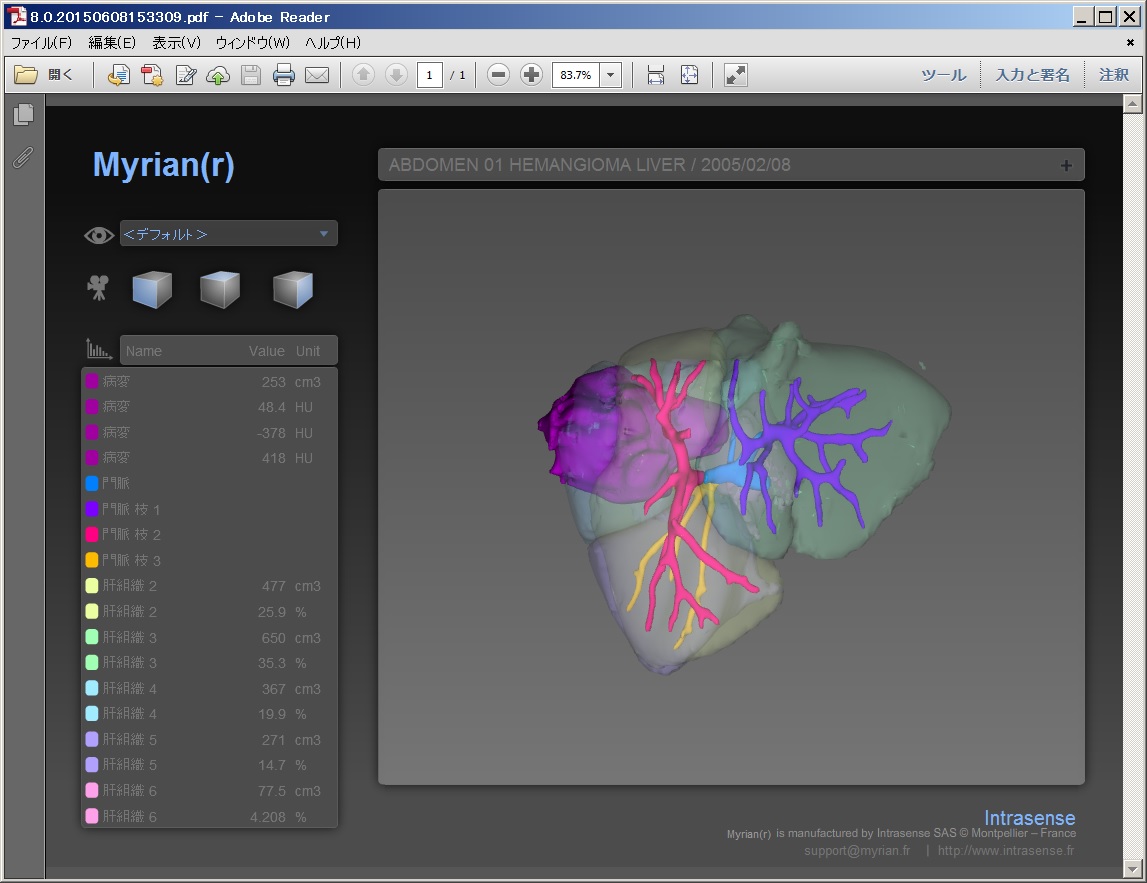

Myrian®XP-Liver 肝臓アプリケーション

世界的な実績と評価を得ている、肝臓解析と手術計画用ソフトウェア

独自に開発された、正確な非剛体レジストレーションと優れたセグメンテーション・アルゴリズムにより肝血管系、肝実質、腫瘍などを数秒で抽出します。

3D PDFによる立体表示ではコミュニケーションの向上に寄与するでしょう。

当製品は3D業界の先駆けとして、世界トップの施設で使用されています。

| 6.3D PDF,ワードなど柔軟な レポート |

|

|